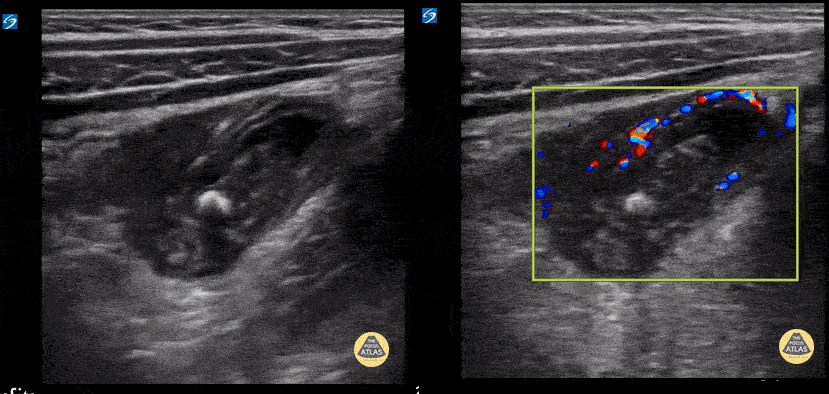

3y female with 3d RLQ abd pain, emesis, fever. WBC 8.5 with 73% PMN. CRP 9. POCUS with enlarged appendix with loss of bowel wall architecture, surrounding early fluid collection, fecolith, and mural hyperemia. Contributor: Matthew Moake, MD PhD